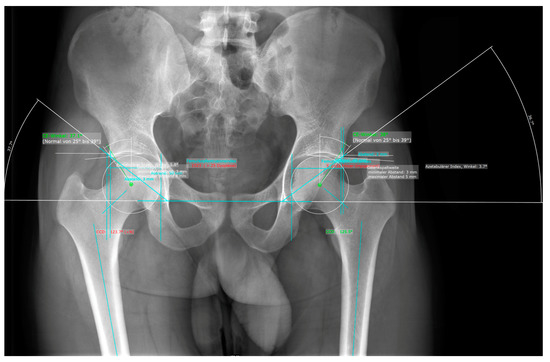

| Yang et al., 2020 [22] | Feasibility Study for automated measurement of the hip joint (determination of CE, Tönnis angle, Sharp angle, FHEI) | Identification of bony landmarks. A total of 1060 ap hip radiographs used for training, and 200 used for testing. Compared to three radiologists. | PCK: 87–100%, ICC: 0.8–0.93, r: 0.83–0.93, RMSE: 0.02–3.27, MAE: 0.02–1.79. |